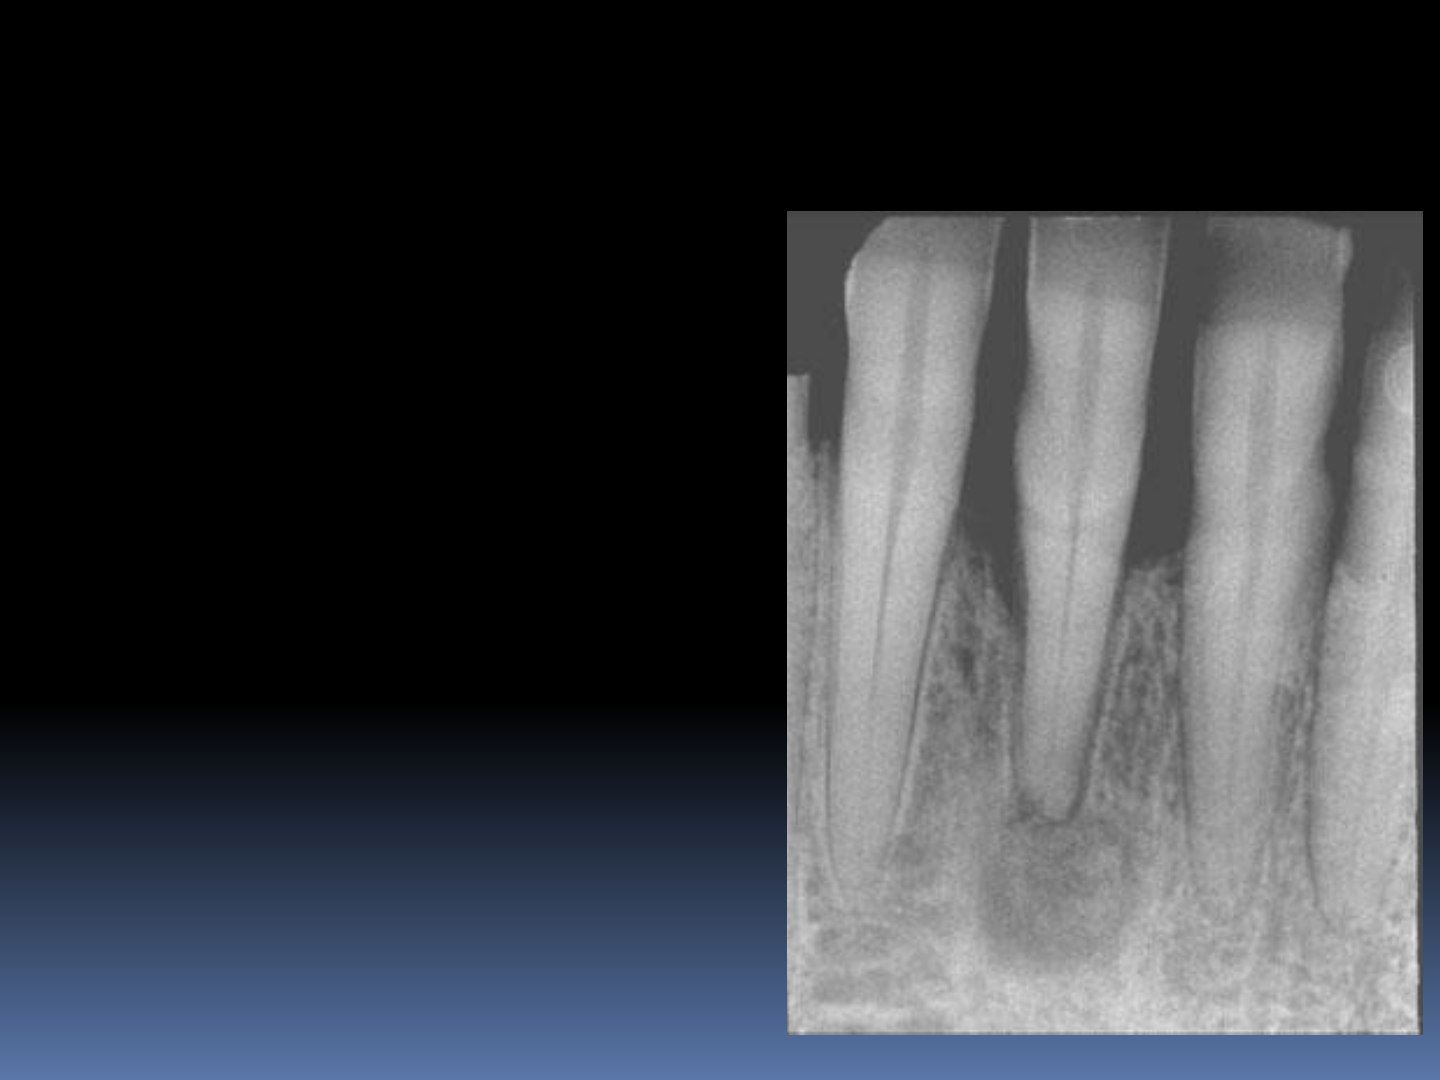

Importância dos aspectos imaginológicos no plano de tratamento da displasia óssea florida: Relato de caso

Grátis: ASPECTO RADIOGRAFICOS DAS LESÕES FIBRÓSSEAS E OSTOMIELITES - Material Claro e Objetivo em PDF para Estudo Rápido